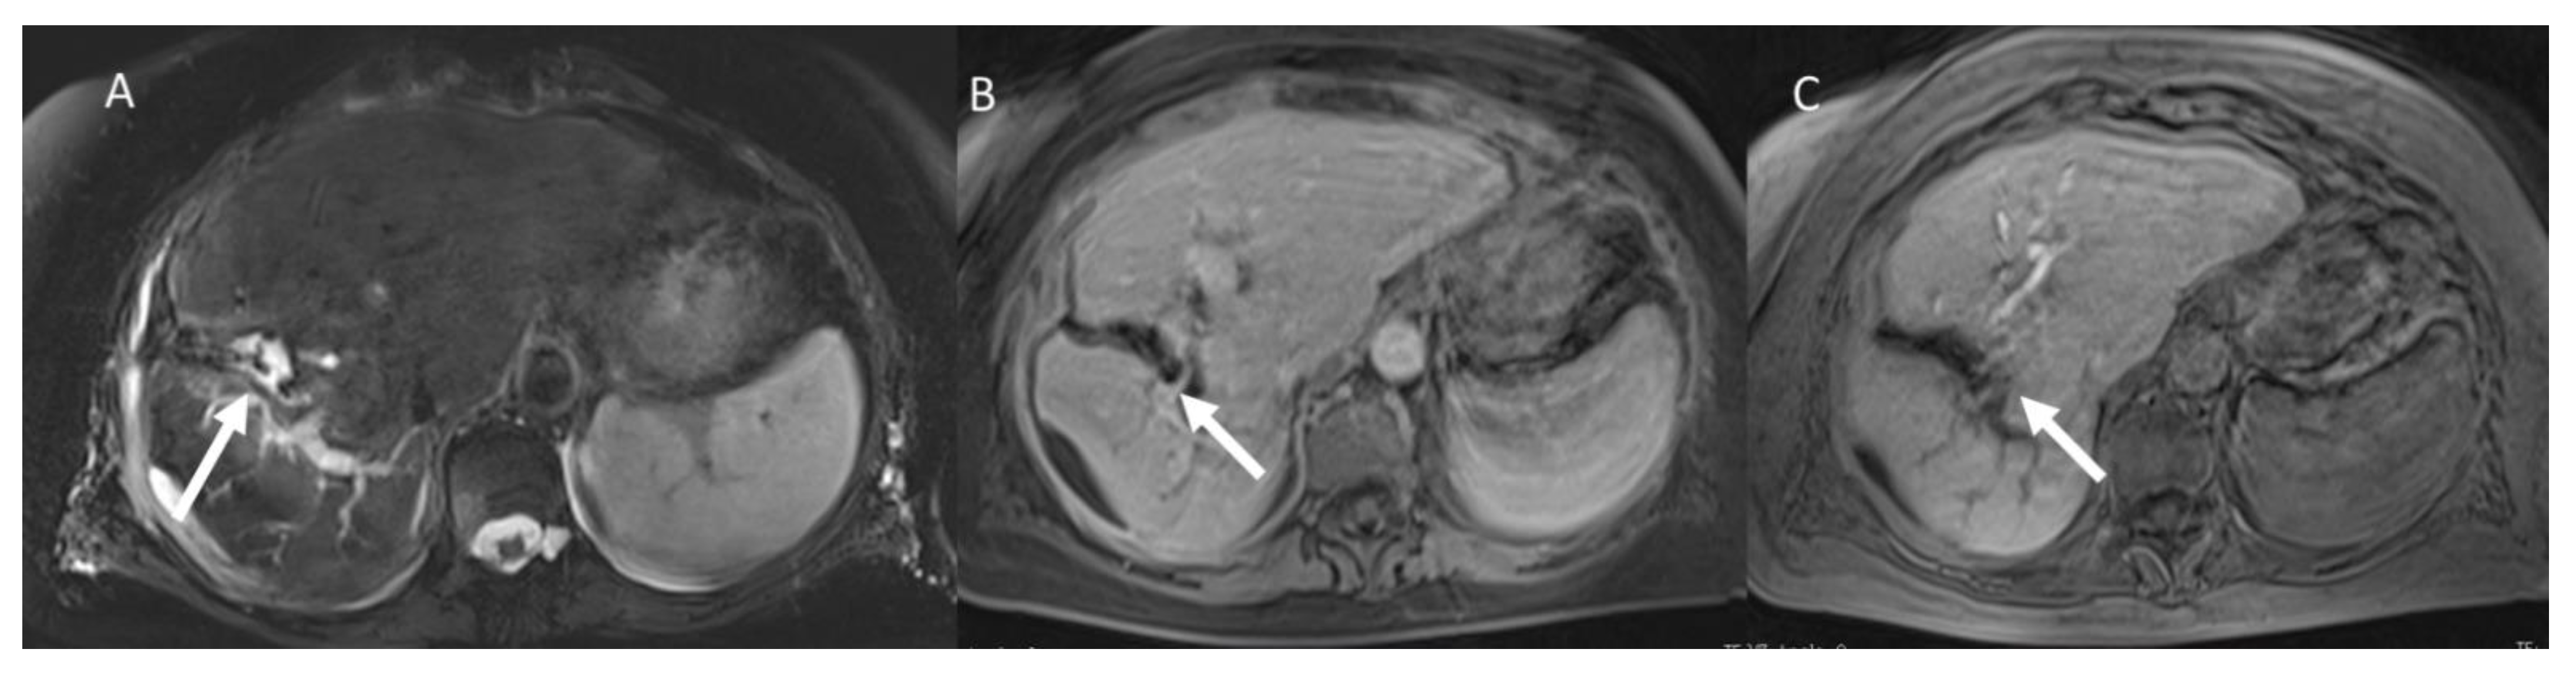

- Granata, V.; Grassi, R.; Fusco, R.; Setola, S.; Belli, A.; Piccirillo, M.; Pradella, S.; Giordano, M.; Cappabianca, S.; Brunese, L.; et al. Abbreviated MRI Protocol for the Assessment of Ablated Area in HCC Patients. Int. J. Environ. Res. Public Health 2021, 18, 3598. [Google Scholar] [CrossRef]

- Granata, V.; Grassi, R.; Fusco, R.; Setola, S.V.; Belli, A.; Ottaiano, A.; Nasti, G.; La Porta, M.; Danti, G.; Cappabianca, S.; et al. Intrahepatic cholangiocarcinoma and its differential diagnosis at MRI: How radiologist should assess MR features. Radiol. Med. 2021, 126, 1584–1600. [Google Scholar] [CrossRef]